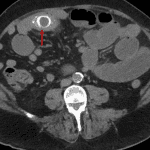

- Distended, fluid-filled loops of proximal and mid small bowel measuring up to 4.5 cm in diameter with transition point in the right lower quadrant where there are several peripherally calcified intraluminal structures

- Gallstone ileus

Findings concerning for acute cholecystitis complicated by gallstone ileus with several gallstones in the distal small bowel and mild upstream small bowel dilation. Recommend surgical evaluation.